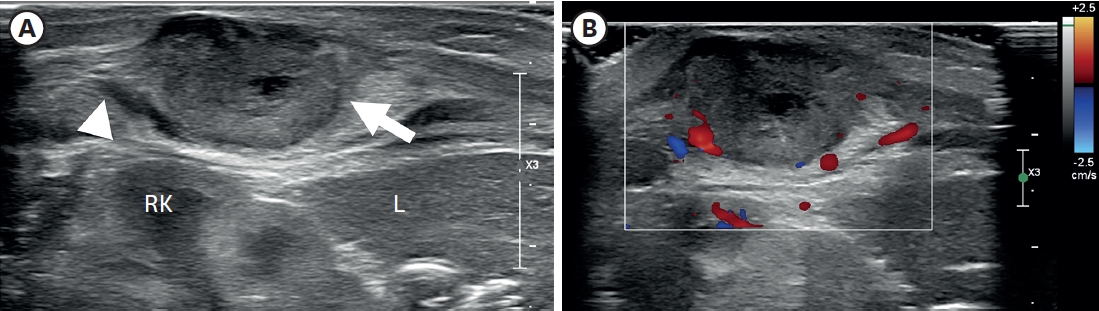

Hirschsprung Disease Associated With Pelvic Neuroblastoma: A Rare Neurocristopathic Association

Sravanthi Vutukuru, Nitin J Peters, Shailesh Solanki, Amita Trehan, Kirti Gupta, Monika Bawa

Adv Pediatr Surg 2024;30(1):32-37.   Published online January 29, 2024

DOI: https://doi.org/10.13029/aps.2024.30.1.32

Hirschsprung disease (HSCR) is a genetic disorder with an incidence of 1:5000, seen in the pediatric age group. The association between HSCR and neuroblastoma (NBL), ends of the neurocristopathy spectrum is rare. Less than 10 cases of this association are reported in the literature and the association between the Phox gene and Sox10 gene in the pathophysiology of these is being studied. We report a one-year-old baby, who presented to us, with chronic constipation on regular enemas and laxative usage. There was a history of delayed passage of meconium. At the time of Duhamel’s pull through a well-defined, bilobed hard presacral mass, was encountered. Excision and coccygectomy were done and the pull was completed. The histopathology showed a well-differentiated NBL. Fludeoxyglucose positron emission tomography scan and the N-Myc amplification were negative and the patient was managed with expectant treatment. She is doing well over a 3-year follow-up with no recurrence and good resolution of bowel functions.